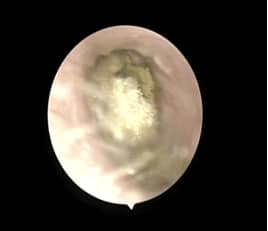

耳真菌感染稱為外耳道真菌病或霉菌性外耳道炎,是真菌侵入外耳道或外耳道內(nèi)的條件致病性真菌,在適宜的條件下繁殖,引起的外耳道的炎性病變。

耳道真菌病可以發(fā)生在任何年齡,以成人為多見(jiàn),是一種慢性或亞急性傳染病,為真菌進(jìn)入外耳道后繁殖生長(zhǎng)所引起的一種皮膚感染,多局限于外耳,也可經(jīng)穿孔的鼓膜侵入中耳及乳突術(shù)腔。

2、由于真菌大量繁殖,堆積形成團(tuán)塊可阻塞外耳道引起阻塞感。

3、真菌團(tuán)塊刺激,外耳道可有少量分泌物,患者感外耳道潮濕。

4、外耳道的脫落上皮和菌絲體等混合、阻塞外耳道而影響聽(tīng)力的傳導(dǎo),或與鼓膜相碰撞摩擦而產(chǎn)生聲響,患者可有聽(tīng)覺(jué)障礙,耳鳴,甚至侵襲鼓膜導(dǎo)致眩暈。